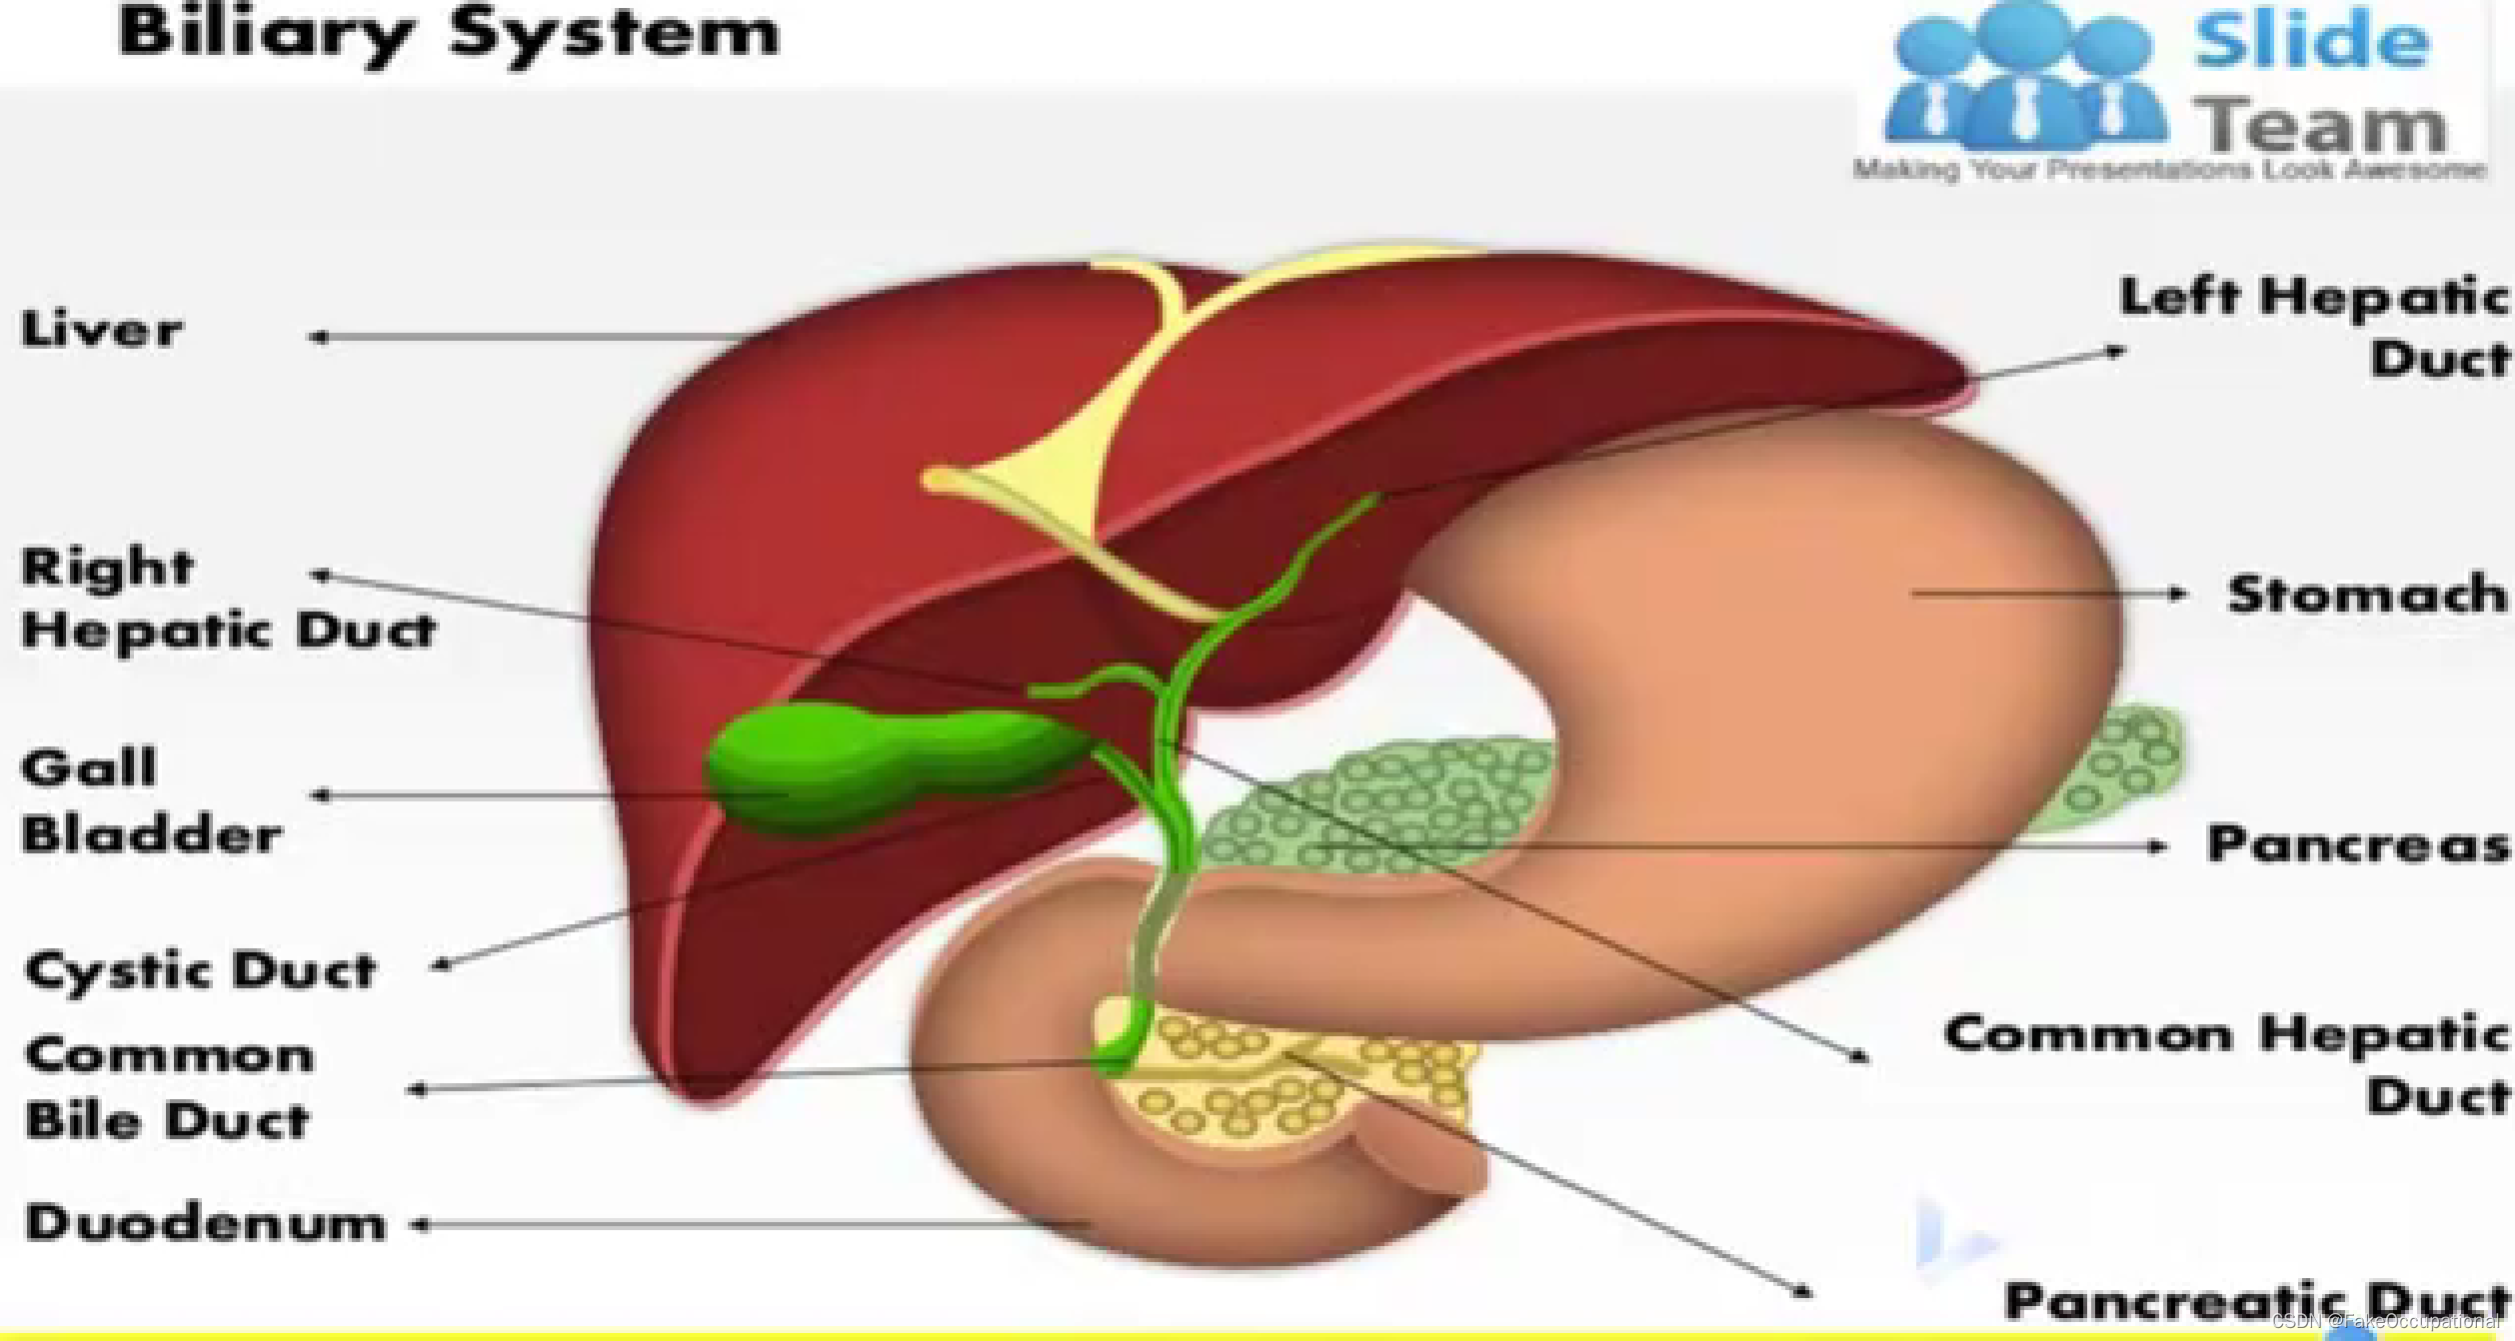

胆道系统解剖(和谐)

胰腺解剖及正常声像图

- 胰腺解剖与生理

腹膜后脏器 、无包膜、次于肝脏的大消化腺重约75克分内分泌部与外分泌部: 内分泌部分泌胰岛素,调节人体血糖浓度,外分泌部分泌胰液,有分解脂肪、蛋白质糖类的作用

位置: 胰腺的体表投影在脐上5cm-10cm处,位于第一第二腰椎体前方,胰尾直达脾门.形态和分部:分为头、颈、体、尾四部分。大致分为蜂料型(最常见) 、腊肠型、哑铃型,

主胰管起至胰尾横贯胰腺,在胰头部胰管和胆总管汇合,开口于十二指肠乳头。副胰管短细,超声难以显示